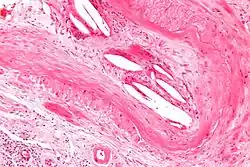

Micrograph showing a cholesterol embolus in a medium sized artery of the kidney. Kidney biopsy. H&E stain. | |

The microscopic examination of tissue (histology) gives the definitive diagnosis. The diagnostic histopathologic finding is intravascular cholesterol crystals, which are seen as cholesterol clefts in routinely processed tissue (embedded in paraffin wax).[7] The cholesterol crystals may be associated with macrophages, including giant cells, and eosinophils.

The sensitivity of small core biopsies is modest, due to sampling error, as the process is often patchy. Affected organs show the characteristic histologic changes in 50-75% of the clinically diagnosed cases.[3][5] Non-specific tissue findings suggestive of a cholesterol embolization include ischemic changes, necrosis and unstable-appearing complex atherosclerotic plaques (that are cholesterol-laden and have a thin fibrous cap). While biopsy findings may not be diagnostic, they have significant value, as they help exclude alternate diagnoses, e.g. vasculitis, that often cannot be made confidently based on clinical criteria.